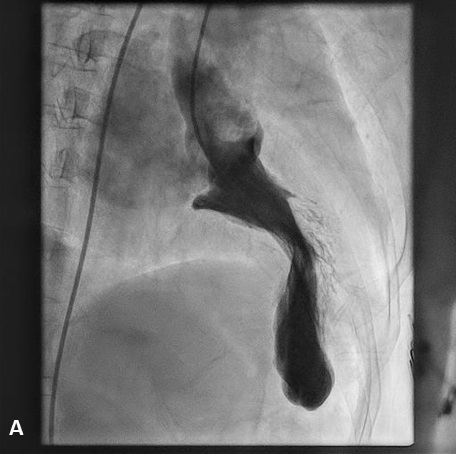

After obtaining informed consent, the patient was taken up for a left heart catheterization and coronary angiography to look for an appropriate septal branch for alcohol septal ablation. The left ventricular systolic pressure was significantly elevated (LVESP 250 mm Hg) and the left ventricle (LV)-to-aorta pullback showed an intracavitary gradient of 140 mm Hg, with no left ventricular outflow tract (LVOT)-to-aorta gradient. The LV angiogram showed the “ballerina foot deformity”, which represents the asymmetrical septal hypertrophy with LV hypercontractility; and severe mitral annular calcification with grade 3 mitral regurgitation (Figure, Videos 1 and 2). Her coronary angiography revealed a significant obstructive disease in the mid-left anterior descending artery (LAD), while the rest of the vessels were normal. After discussion with the heart team, she was taken up for alcohol septal ablation, which successfully decreased the LVOTO gradient to 25 mm Hg. Subsequently, percutaneous coronary angioplasty to the LAD was done successfully and the patient was discharged with significant symptomatic relief.

Ballerina foot appearance is a long-described LV angiography sign in hypertrophic obstructive cardiomyopathy that reflects LV hypercontractility with a resultant narrow LV systolic cavity, resembling a ballet dancer’s feet. The eponym has also been used to describe the appearance of basal LV hypercontractility and the visibly prolapsing leaflet on LV angiography in mitral valve prolapse syndrome.